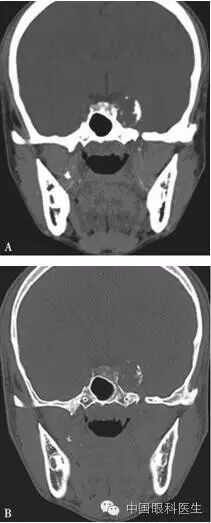

体格检查:双眼矫正视力0.8。右眼眼睑位置及眼球运动均正常,左眼上睑下垂,遮盖瞳孔上半部分,提上睑肌肌力4mm,左眼不能外展,上转、下转、内收运动均部分受限。患者右眼瞳孔直径3mm,左眼4mm;右眼对光反射灵敏,左眼迟钝,RAPD(-)。双眼眼底、眼压均正常。视觉诱发电位(visual evoked potential,VEP)、视野检查均未见明显异常。头颅MRI平扫+增强结果显示,左侧鞍旁海绵窦内T1WI稍低信号、T2WI稍高信号影,大小为21mm×23mm×22mm,增强扫描病灶呈不均匀强化,内可见多发的未强化区,左侧颈动脉海绵窦段受压外移,但结构未见明显损害(图2-3-0-1)。头颅CT平扫显示左侧鞍旁密度减低影,CT值为21Hu,大小为2.3cm,边缘可见钙化影,双侧眶内和球后未见异常(图2-3-0-2)。患者转入神经外科并行经额颞颧弓硬膜外入路左侧海绵窦区占位性病变切除术。术中快速冰冻切片病理学检查示,切除的组织标本富含黏液,制片困难。术后病理报告:左侧海绵窦区软骨源性肿瘤。考虑软骨瘤可能性大,局部细胞生长活跃,细胞间质伴黏液变性,免疫组织化学染色显示,肿瘤细胞对S-100和CK均呈阴性反应(图2-3-0-3)。术后患者左眼视力下降,额部及颊部皮肤感觉迟钝。眼科检查:右眼检查同术前,左眼矫正视力0.5,角膜上皮粗糙,角膜荧光素染色弥漫性着色,RAPD(-)。检眼镜检查示视盘界清,色红,视网膜血管走行正常,黄斑区未见明显异常。VEP、视野检查均未见明显异常。给予玻璃酸钠滴眼液点左眼、重组牛碱性成纤维细胞生长因子软膏涂左眼结膜囊并给予营养神经、改善全身血液循环药物治疗1周后,检查示见角膜上皮透明,角膜荧光素染色不明显,矫正视力0.8,左眼提上睑肌肌力测试可上提10mm。术后1个月复诊见,上睑下垂治愈,眼球运动受限明显好转。

注:A. T2WI;B.增强扫描。左侧鞍旁海绵窦内可见T1WI稍低信号、T2WI稍高信号影,大小约为21mm×23mm×22mm,增强扫描病灶呈不均匀强化,其内可见多发未强化区,左侧颈动脉海绵窦段受压外移,未见明显侵犯